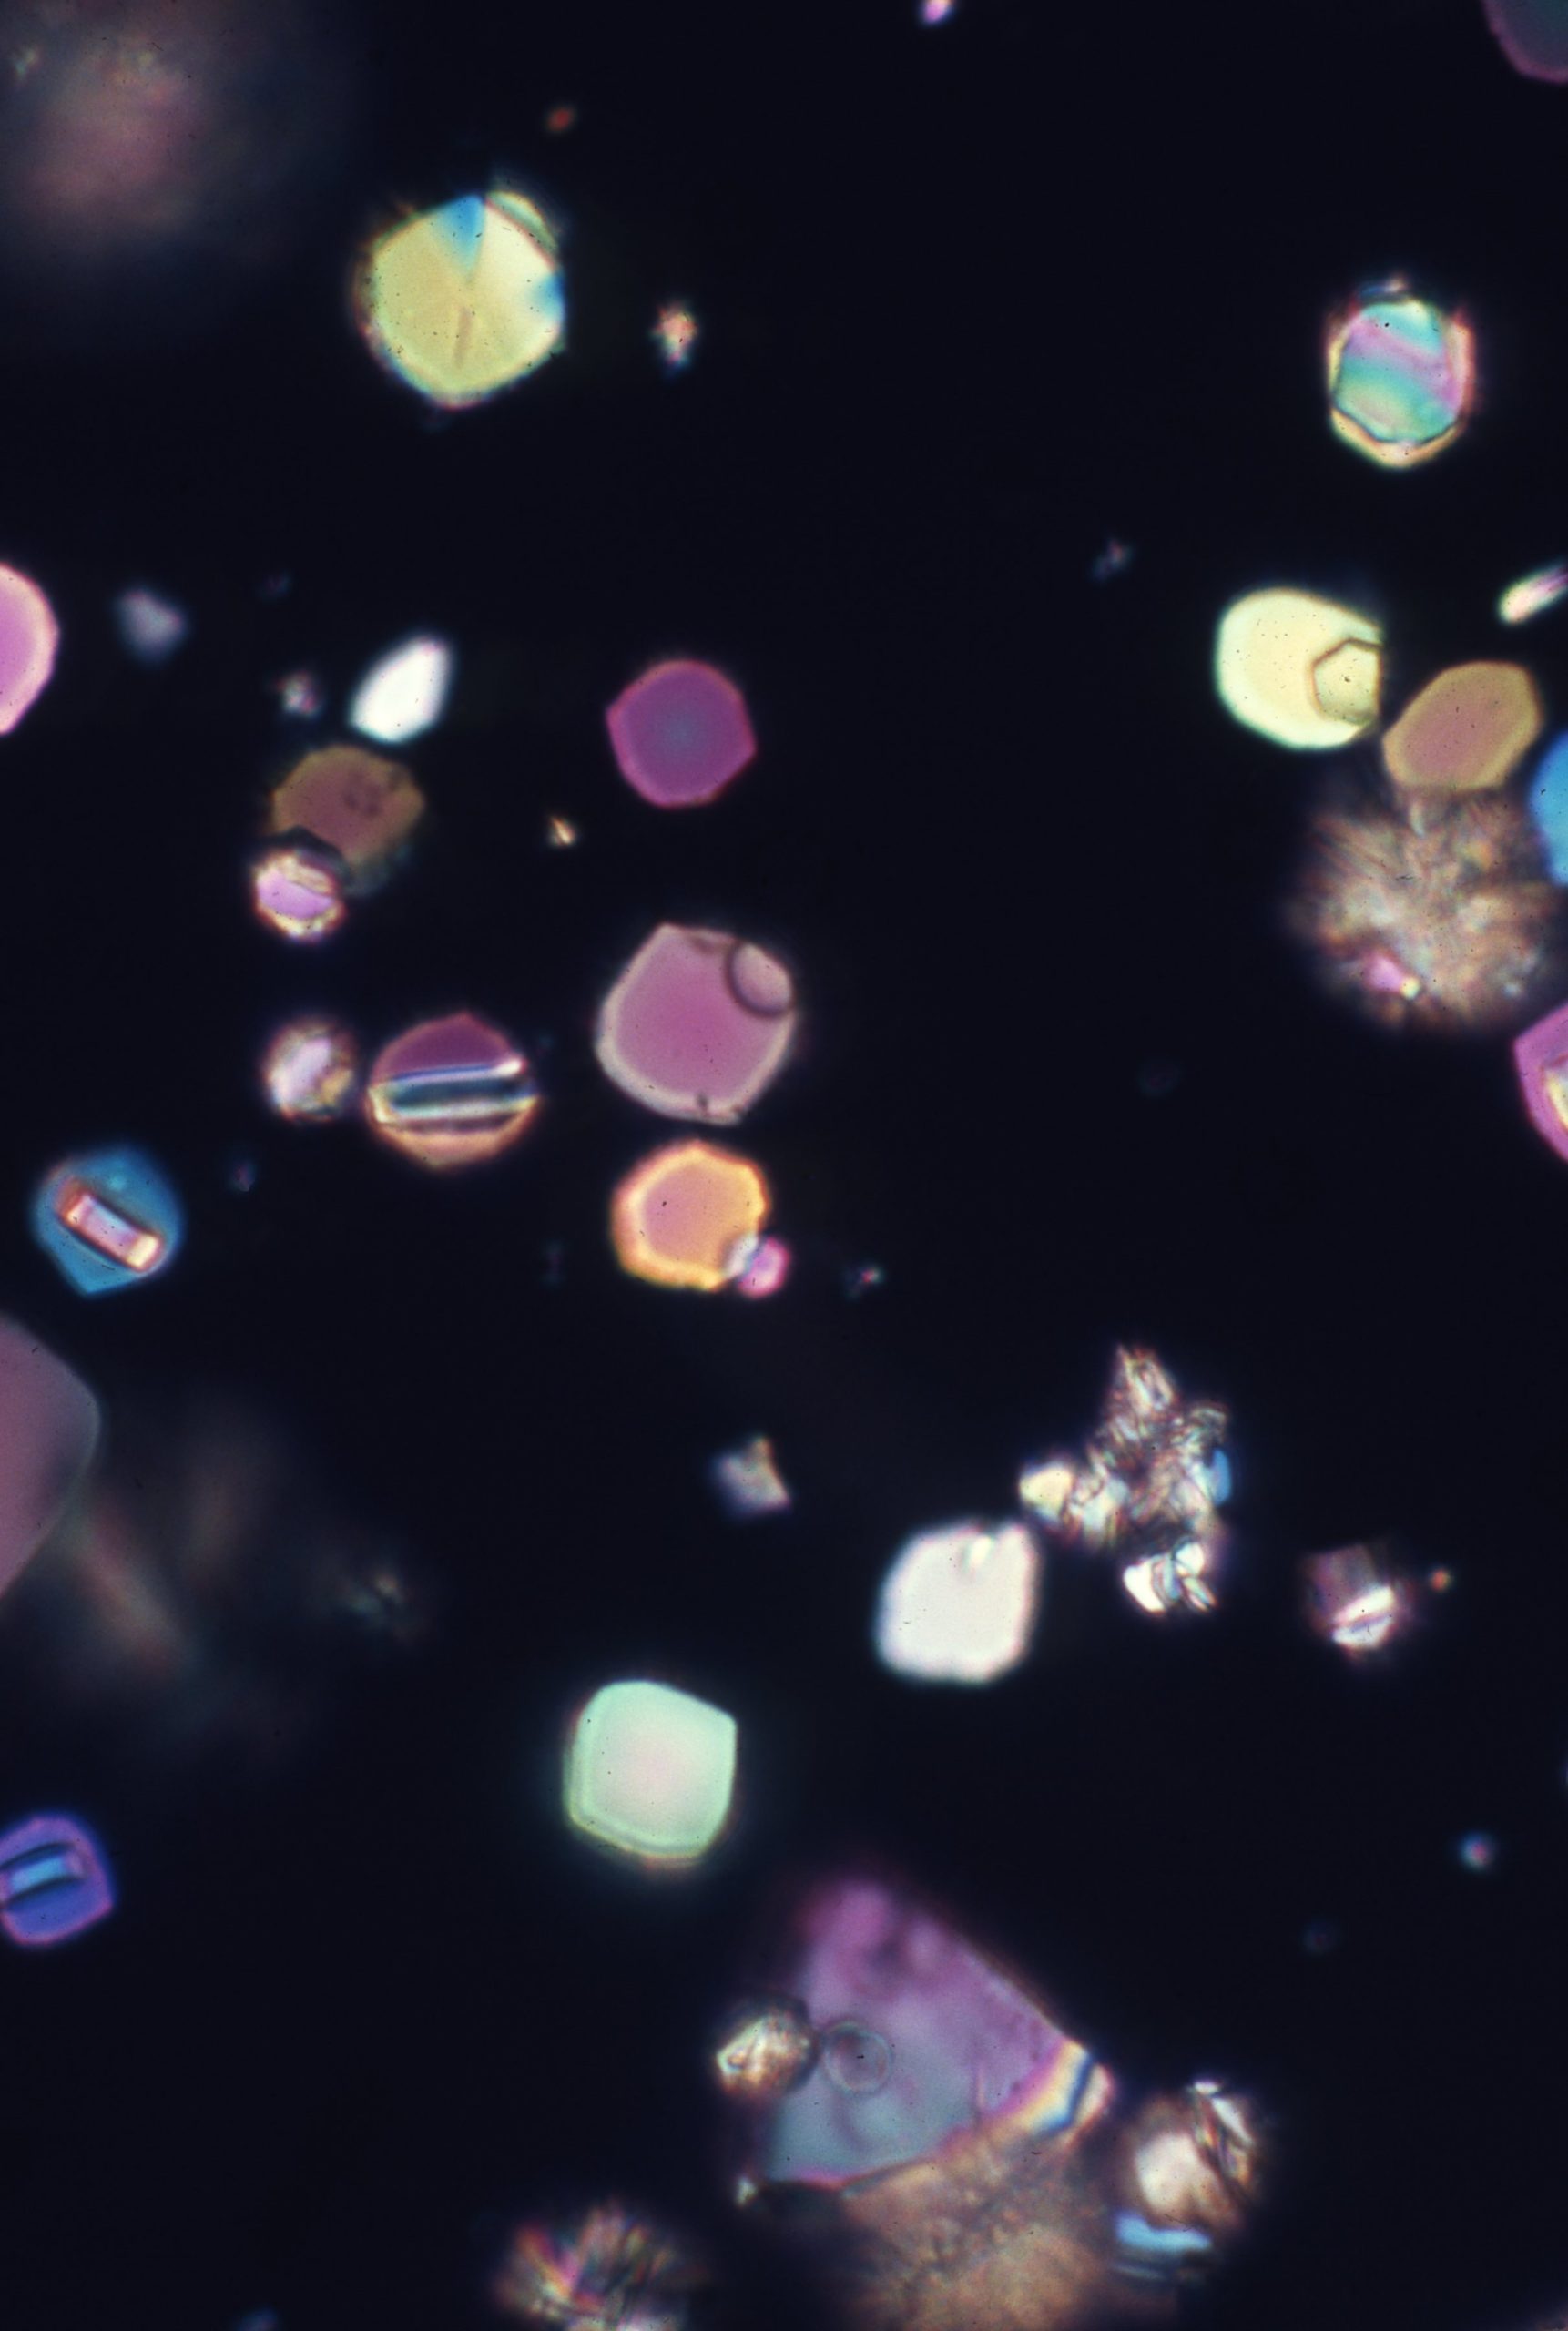

Uric acid crystals are found in acid urine, the crystal vary more in morphology than any other type of crystalThe morpholoy varies from needles, hexagonal, whestone forms, rosttes or rhombic plates Mag 10X Mag 10X Mag 10xX Mag 40X Mag 40X Mag 40X Mag 40x Mag 40X The above microphotographs are uric acid crystal with polarized light